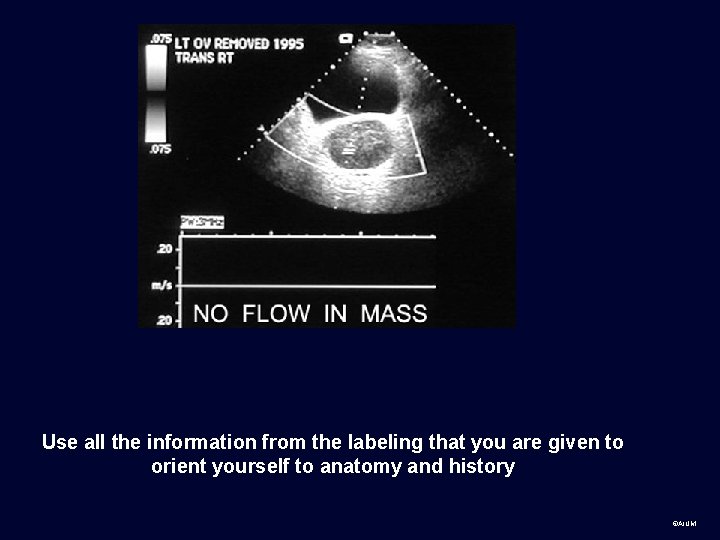

Use all the information from the labeling that you are given to orient yourself to anatomy and history ©AIUM